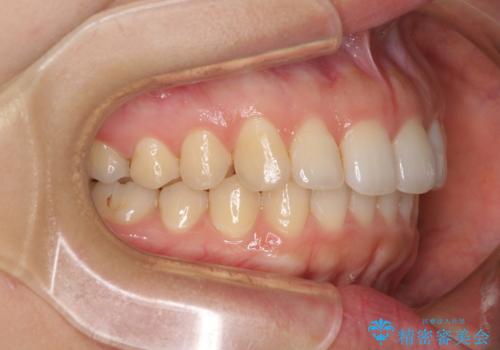

インビザライン矯正で前歯のデコボコを改善

骨格的に下顎骨が左にずれており、上下の正中一致は困難ではありましたが、IPR(歯と歯の間を削る)や後方への移動など組み合わせて、できる限り改善しました。

インビザラインはマウスピースを外している時間が長いと、長期間使用しても前歯のデコボコはあまり改善されません。こちらの患者様は治療期間が長くなり、装着時間が短くなってしまったことで、気になる部分の改善により長期間を要するようになってしまいました。